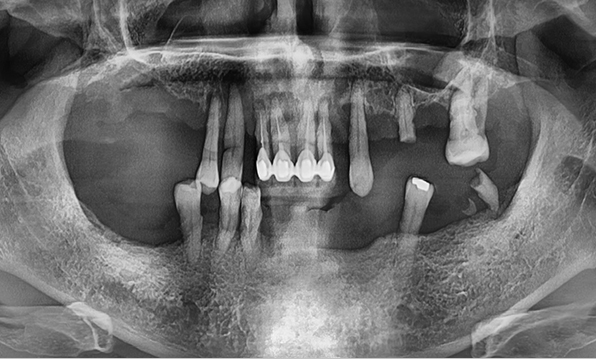

Before & After

| Before | After |